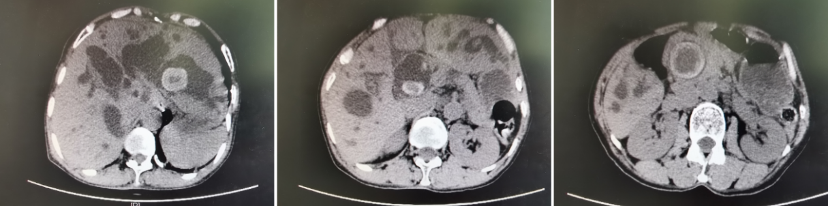

适逢福建省立医院对口帮扶霞浦县医院医联体建立,王奶奶一家人闻悉后,带着期盼而又忐忑不安的心情来到霞浦县医院就诊。CT检查显示:大大小小的石头已经挤满了肝内胆管,在胆总管里也填塞着几颗鹅蛋大小的结石,因为长期的胆汁淤积,肝脏已呈现严重的肝硬化表现,加之经历过多次胆道手术,县医院的医生立即意识到病情的严重性和手术治疗的复杂性。

术前上腹部CT:肝内部分胆管及胆总管多发结石,伴胆道系统明显扩张